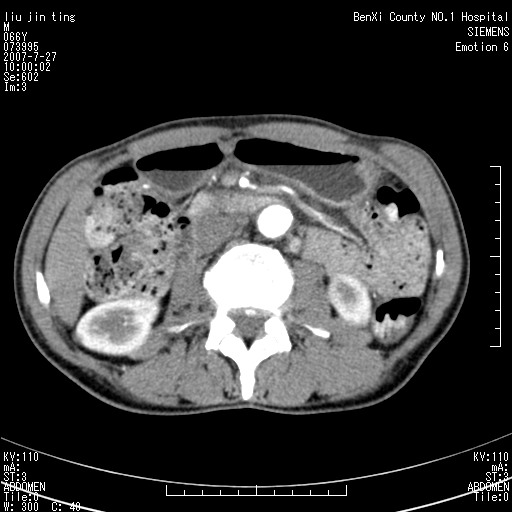

腹痛,背痛,无恶心呕吐,不黄,彩超示胰腺钩癌,ct扫描病灶平扫30-40hu,增强后动脉期40--60hu,静脉期50-68hu,真的是钩突上的么?您要试一试么?

肠系膜根部肿块,淋巴结可能,难道是转移性淋巴结。

沿着肠系膜上动脉呈匍匐性生长的软组织肿块,形态不规则,包绕肠系膜上动脉,呈明显强化,考虑来源于肠系膜的恶性肿瘤

肠系膜根部肿块,累及肠系膜上动脉,考虑肿大淋巴结累及肠系膜上动脉.

腹腔干至肠系膜上动脉水平肿大淋巴结影可能性大.

钩突是正常的,只见腹膜后淋巴结的肿大,考虑淋巴瘤或转移可能。

腹膜后占位性病变,首先考虑肿大淋巴结。